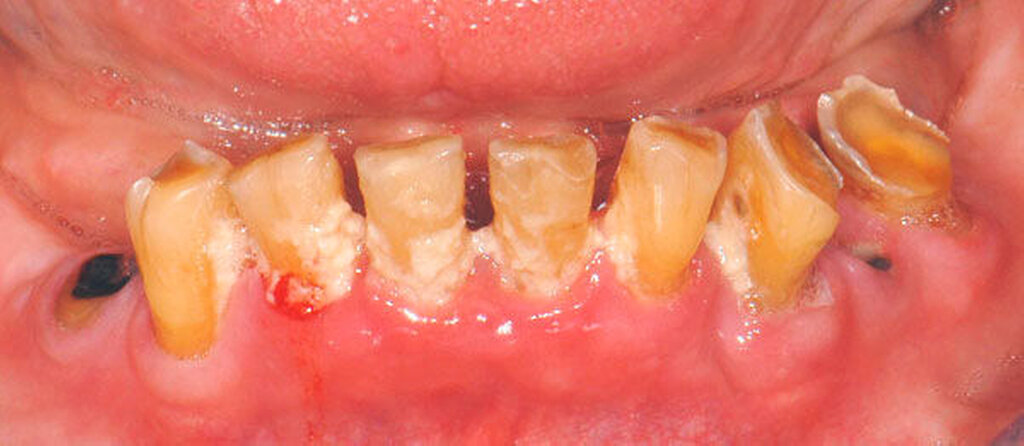

Bei älteren Patienten mit (infolge geistiger Einschränkung) vernachlässigter Mundhygiene, exemplarisch in Abbildung 5 dargestellt, wird zuweilen eine Extraktion sämtlicher Zähne vorgenommen. Eine anschließende prothetische Versorgung ist in solchen Fällen wegen mangelnder Adaptationsfähigkeit oftmals nicht mehr möglich. Dies hat zur Konsequenz, dass die Betroffenen in ihrem Aussehen, ihrer Sprachfunktion und ihrer Fähigkeit zur Nahrungsaufnahme noch eingeschränkter sind als vorher, verbunden mit vielerlei Nachteilen im psycho-sozialen Umfeld.

Wenn irgend möglich, sollte deshalb erwogen werden, einen Erhaltungsversuch wenigstens bei den gut zugänglichen Schneide- und Eckzähnen vorzunehmen, auch wenn die Prognose unsicher ist und Rezidive der Wurzelkaries zu erwarten sind. Die in Abbildung 5 gezeigte Patientin lebte zunächst noch zu Hause und wurde von einer Pflegeperson täglich betreut. Nach Umzug in ein Pflegeheim wird sie von ihrer ehemaligen Pflegerin nach wie vor ein- bis zweimal wöchentlich aufgesucht. Die Pflegerin nimmt bei ihr ein- bis zweimal wöchentlich eine Zahnreinigung mittels Zahnbürste und Interdentalraumbürsten vor, was mit einem Zeitaufwand von jeweils maximal fünf bis zehn Minuten verbunden ist. Obwohl sich nach zwei Jahren an einigen Zähnen ein Kariesrezidiv eingestellt hat, konnte der Zahnbestand gehalten werden.